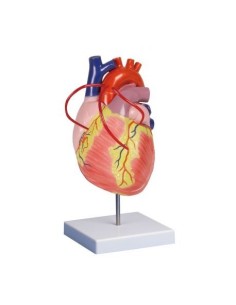

Du crâne en 22 parties à verrouillage magnétique aux modèles de colonne vertébrale, des modèles d'articulation aux modèles de cœur, chaque pièce de notre collection est conçue pour une immersion totale dans l'étude de l'anatomie humaine. Nos modèles, réalisés à partir de scans d'os réels, garantissent une expérience tactile authentique et une fidélité de poids presque identique aux originaux.